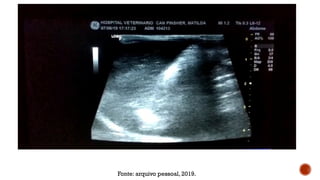

Fonte: arquivo pessoal, 2019.